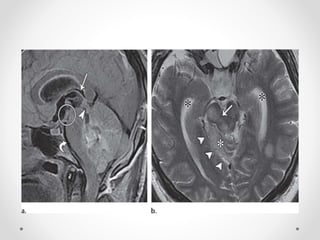

Subdural hematoma after a hemodialysis session in a 26-year-old man with a history of

end-stage kidney disease. The right pupil was dilated and unresponsive to light. Axial

CT image shows the uncus displaced downward across the tentorial incisura (curved

arrow). The ipsilateral perimesencephalic cistern (double-headed arrow) is widened,

and the contralateral cistern is compressed. Note the contralateral dilatation of

the temporal horn of the lateral ventricle (*).

- DTH in a 38-year-old man with an acute head injury and left subdural hematoma. There is

right shift and mild rotation of the brainstem. (a) Axial nonenhanced CT image shows widening of the

left basal cistern (arrow) and effacement of the right basal cistern (dashed line), as well as dilatation of the

temporal horn of the right lateral ventricle (*). (b) CT image shows compression and rotation of the midbrain, which

appears elongated (arrowheads). There is complete obliteration of the perimesencephalic

cisterns. Note the widening of the opposite ventricular atrium and temporal horn (*).